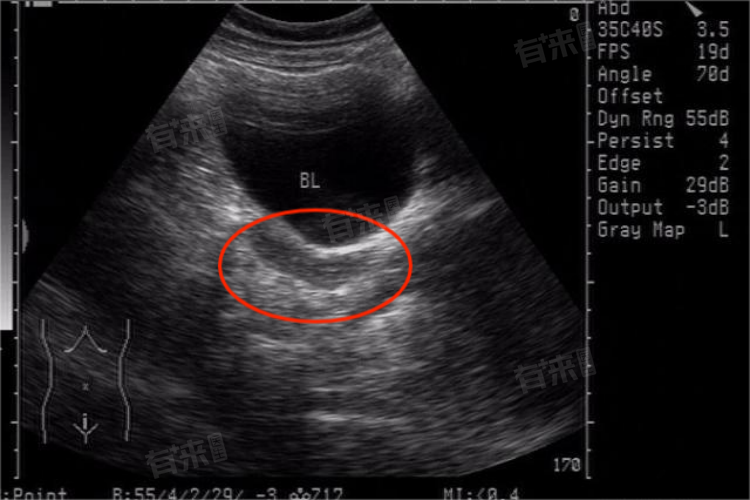

- 查看怀孕相关状况:在怀孕早期B超可以确定是否为宫内妊娠,排除宫外孕的可能。可以看到孕囊的位置、大小、形态,以及是否有胎芽和胎心搏动,在孕期还可以监测胎儿的生长发育情况、胎盘的位置和成熟度、羊水量的多少等。

- 排查多种子宫病变:可以检测出子宫腔内是否存在异物,如节育环的位置是否正常、是否有残留的妊娠组织等,对于怀疑有子宫内膜癌的患者,B超可能显示子宫内膜增厚、回声异常,宫腔内有不规则的肿块等。